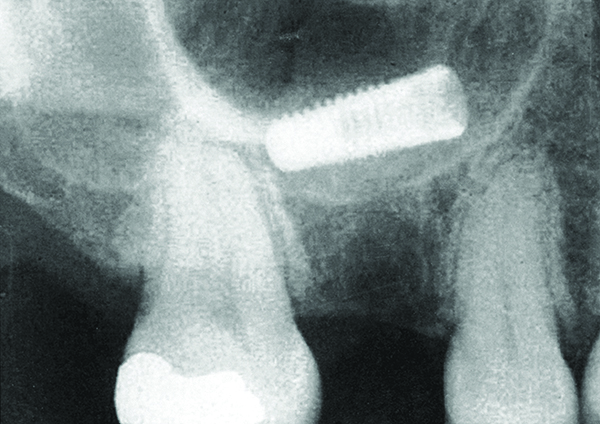

A fractured implant is classified as an intermediate complication

Figure 1